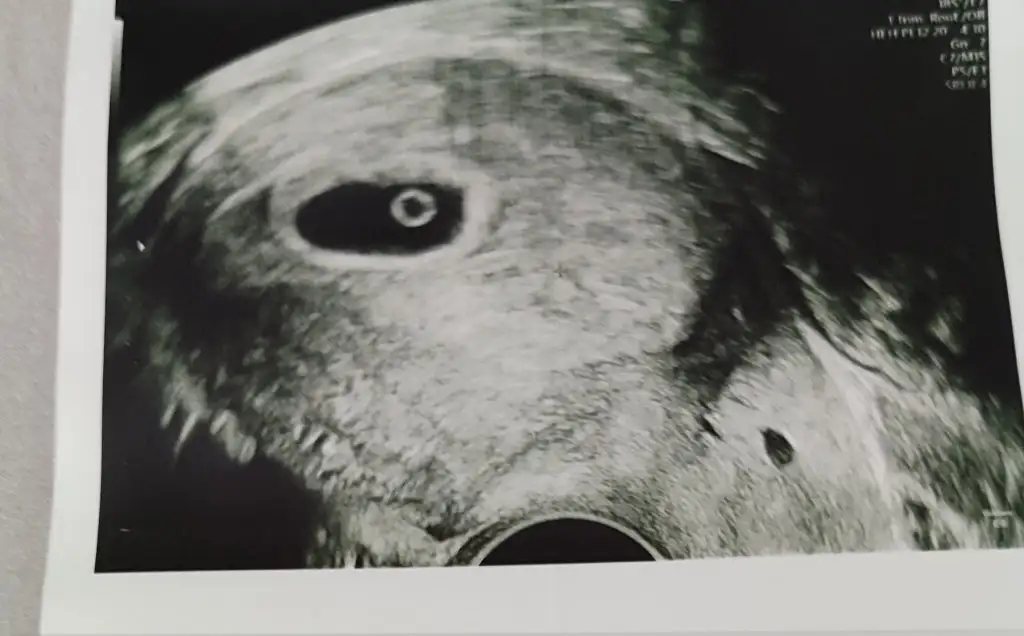

İlk gittiğim zaman benim de öyleydi 6 haftalıkken sadece kese vardı bebek yoktu şimdi 8+2deyiz bir kaç gün gittim bebişin kalp atışını bile duyduk merak etme sendeHanımlar iyi akşamlar, son adet tarihine göre 6+5 gebeyim. Bugün ilk kez doktora gittik. Kese filan göründü ama bebek yokdoktor geç döllenme de olabilir, boş gebelik de haftaya tekrar gel dedi. Anlayan var mıdır bi baksa ultrasona

Doktorlar emin olana kadar duş gebelik boş gebelik ihtimalini değerlendirir öyle yaklaşır hep hatta kalp atışını duyana kadar oh dedirtmez ama sen rahat ol gayet güzel büyüyorlarHanımlar iyi akşamlar, son adet tarihine göre 6+5 gebeyim. Bugün ilk kez doktora gittik. Kese filan göründü ama bebek yokdoktor geç döllenme de olabilir, boş gebelik de haftaya tekrar gel dedi. Anlayan var mıdır bi baksa ultrasona

Canim hemen strese girme belki geç dollendi alttan mi bakti mesela karından da görülmemiş olabilir evet seni anlıyorum bende mesela ilk gittiğimde bebek neden görünmedi diye stres oldum ama görünce rahatlıyorum o kadar stresi boşuna yaptım diyorsun haftaya her şey anlaşılır ve mutlu bi sekilde bize haber verirsinHanımlar iyi akşamlar, son adet tarihine göre 6+5 gebeyim. Bugün ilk kez doktora gittik. Kese filan göründü ama bebek yokdoktor geç döllenme de olabilir, boş gebelik de haftaya tekrar gel dedi. Anlayan var mıdır bi baksa ultrasona